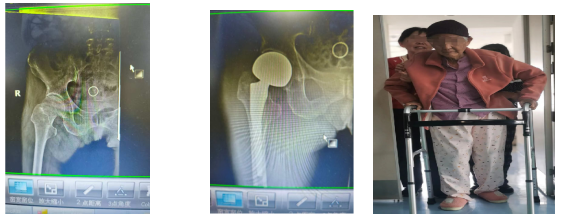

患者2:93岁的薛奶奶既往有冠心病、脑梗死后遗症,贫血、低蛋白血症、慢性胃炎,因摔伤致右侧股骨粗隆间,在骨折剧痛和应激状态下,消化道出血极易发生,手术风险极高。

术前: 术后: